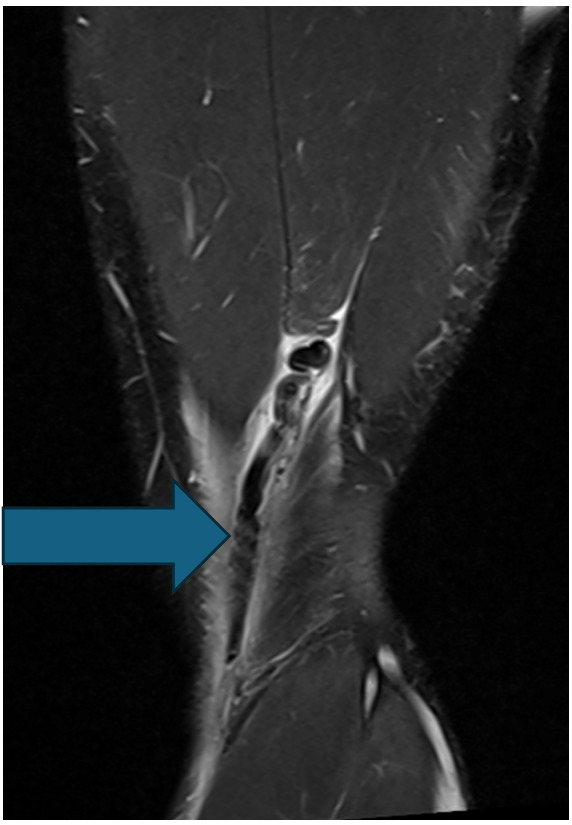

The subject was a 20-year-old male who was actively competing in collegiate American football within the Football Bowl Subdivision – the highest level of collegiate football in the United States. The subject originally sustained an injury to his distal posterior thigh on his nondominant left leg when performing resisted sprinting with a parachute attachment. While decelerating, the athlete slipped during the initial contact phase of his running gait, causing his knee to hyperextend and resulted in immediate posterior thigh pain. The athlete attempted to continue training during the session, however, ultimately discontinued participation due to high levels of pain at the distal posterior thigh. Upon evaluation by the athletic trainer, the athlete presented with pain upon resisted knee flexion and with a palpable defect at the posterior distal thigh. The athlete received an MRI shortly after the injury. The MRI revealed an avulsion of the distal semitendinosus tendon with 4 cm of cranial retraction (Figure 1). After all treatment options were discussed with the athlete and he was presented information regarding the high failure rates of conservative care and evidence of conservative cases with large variability in return to sport time, the athlete chose to proceed with the left distal semitendinosus tendon excision procedure for an expedited return to sport.